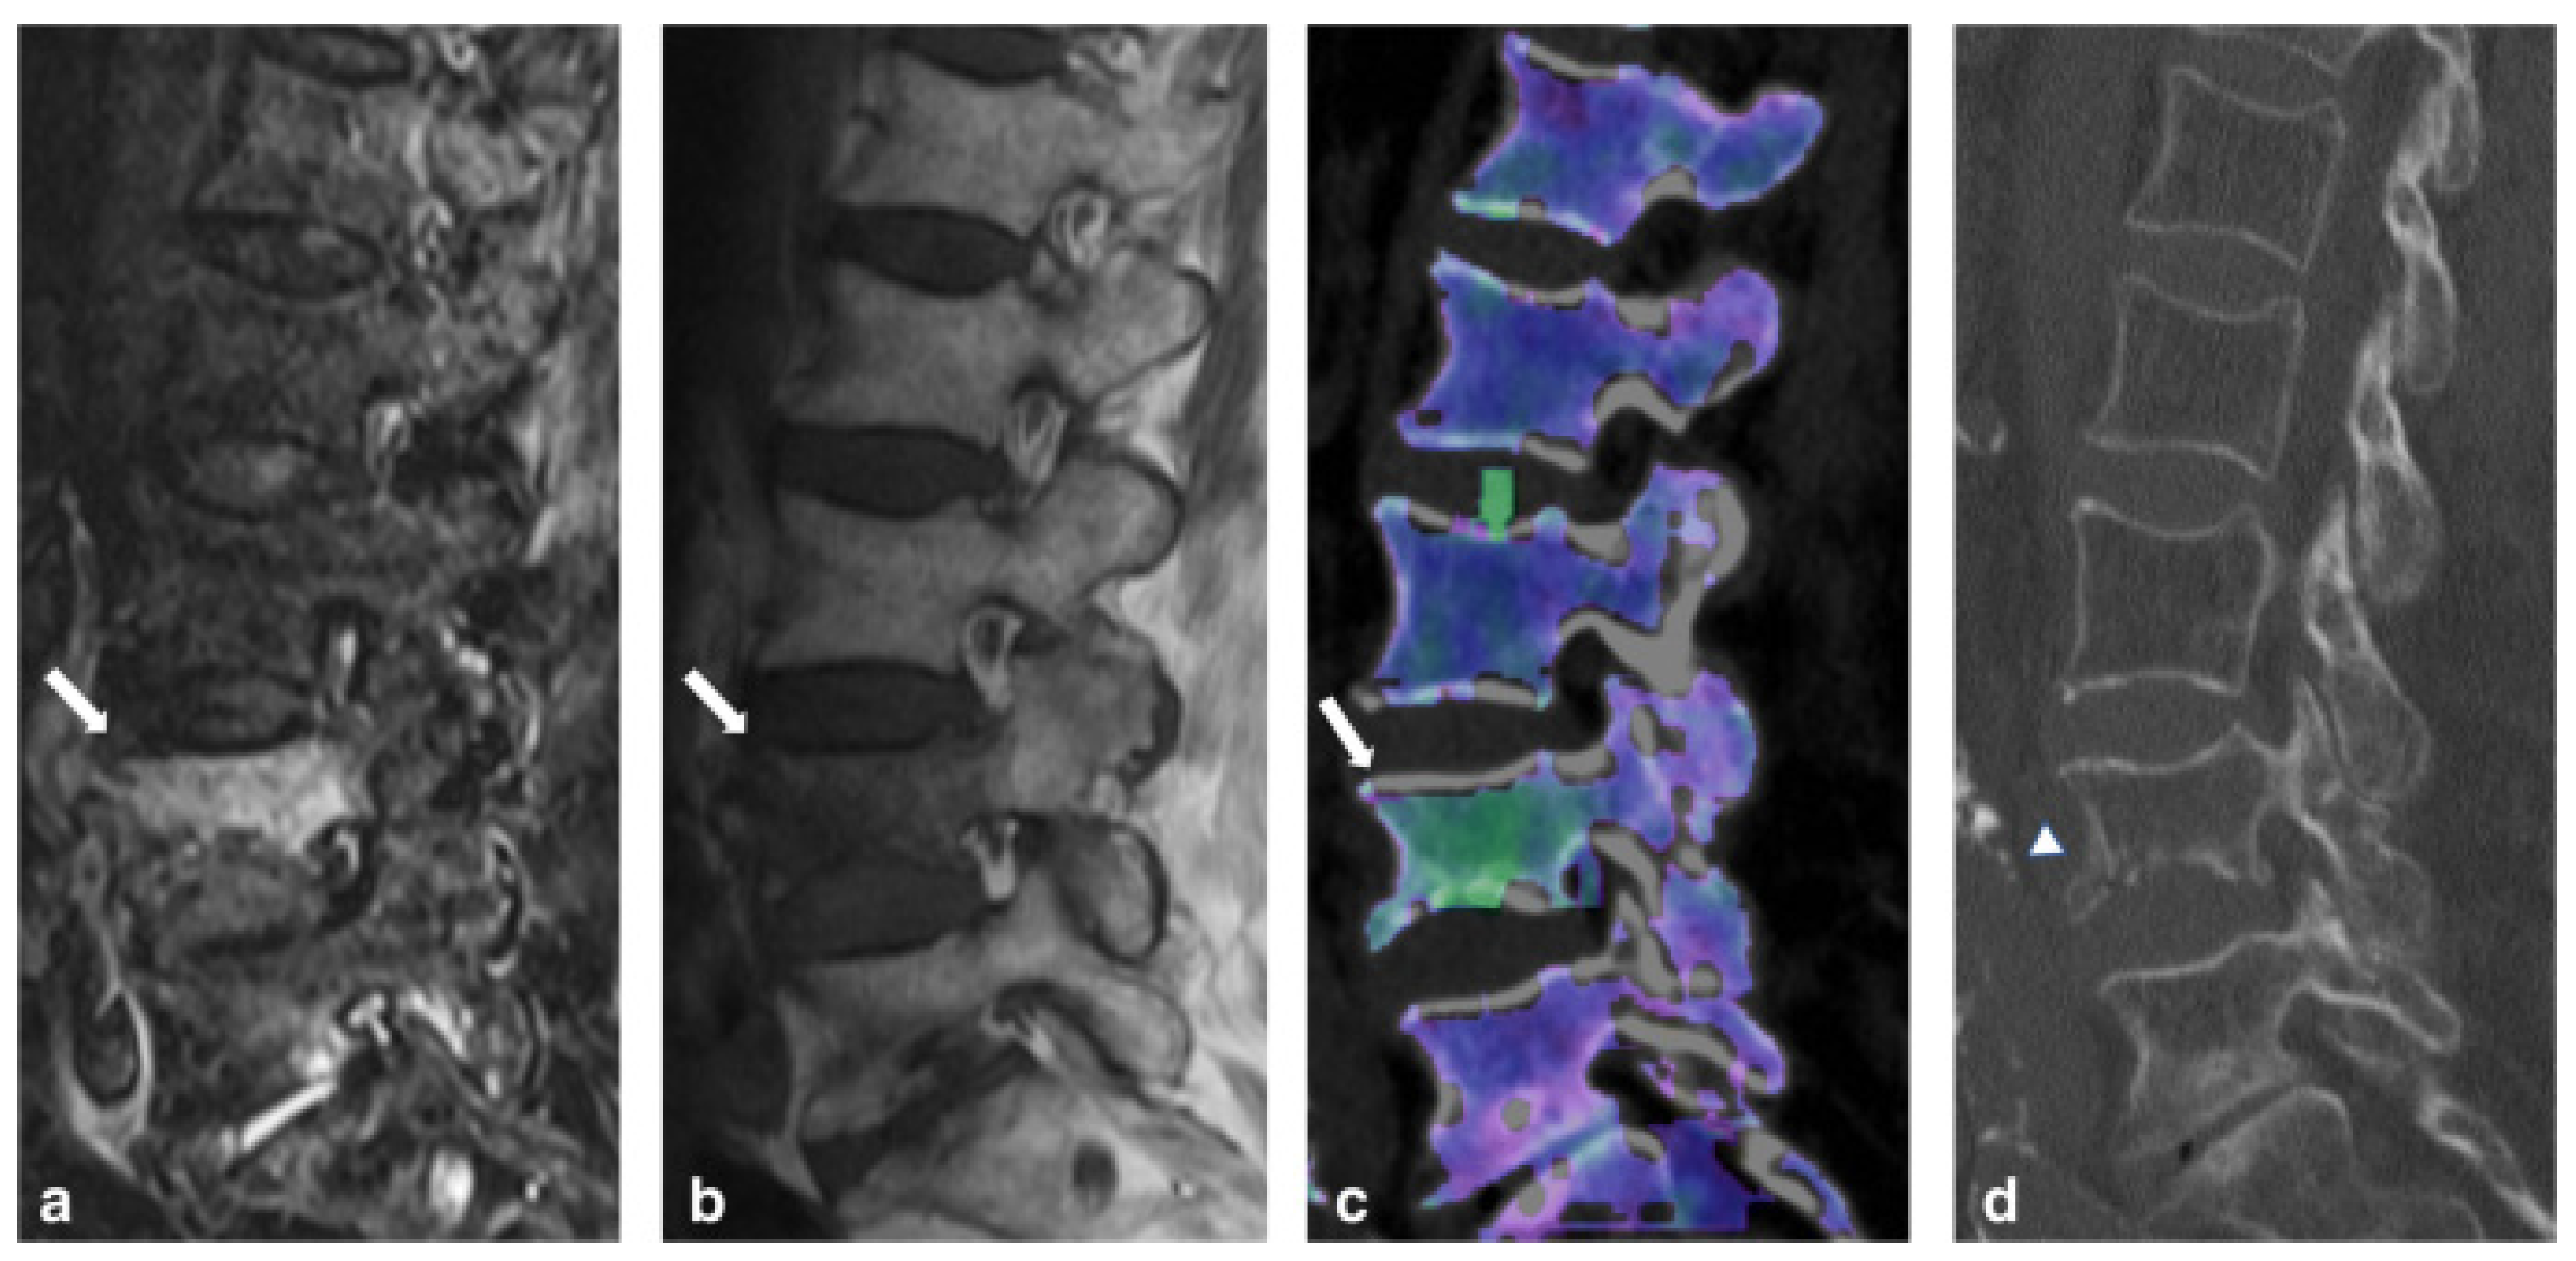

- Cavallaro, M.; D’angelo, T.; Albrecht, M.H.; Yel, I.; Martin, S.S.; Wichmann, J.L.; Lenga, L.; Mazziotti, S.; Blandino, A.; Ascenti, G.; et al. Comprehensive comparison of dual-energy computed tomography and magnetic resonance imaging for the assessment of bone marrow edema and fracture lines in acute vertebral fractures. Eur. Radiol. 2022, 32, 561–571. [Google Scholar] [CrossRef]

- Shinohara, Y.; Sasaki, F.; Ohmura, T.; Itoh, T.; Endo, T.; Kinoshita, T. Evaluation of lumbar intervertebral disc degeneration using dual energy CT virtual non-calcium imaging. Eur. J. Radiol. 2020, 124, 108817. [Google Scholar] [CrossRef] [PubMed]